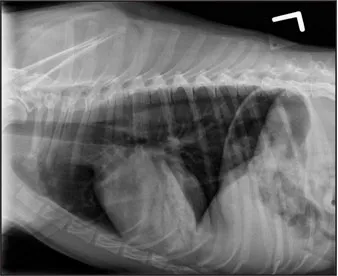

CASE 1.1 A 7-year-old neutered male Labrador Retriever who was hit by a car. You obtain these thoracic radiographs: Figs. 1.1a, b, left and right lateral projections, respectively; Figs. 1.1c, d, ventrodorsal and dorsoventral projections, respectively.

1.1a